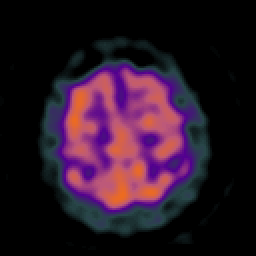

Huntington's Chorea, MR -- Slice #16

[Home][Help][Clinical] Slice 16